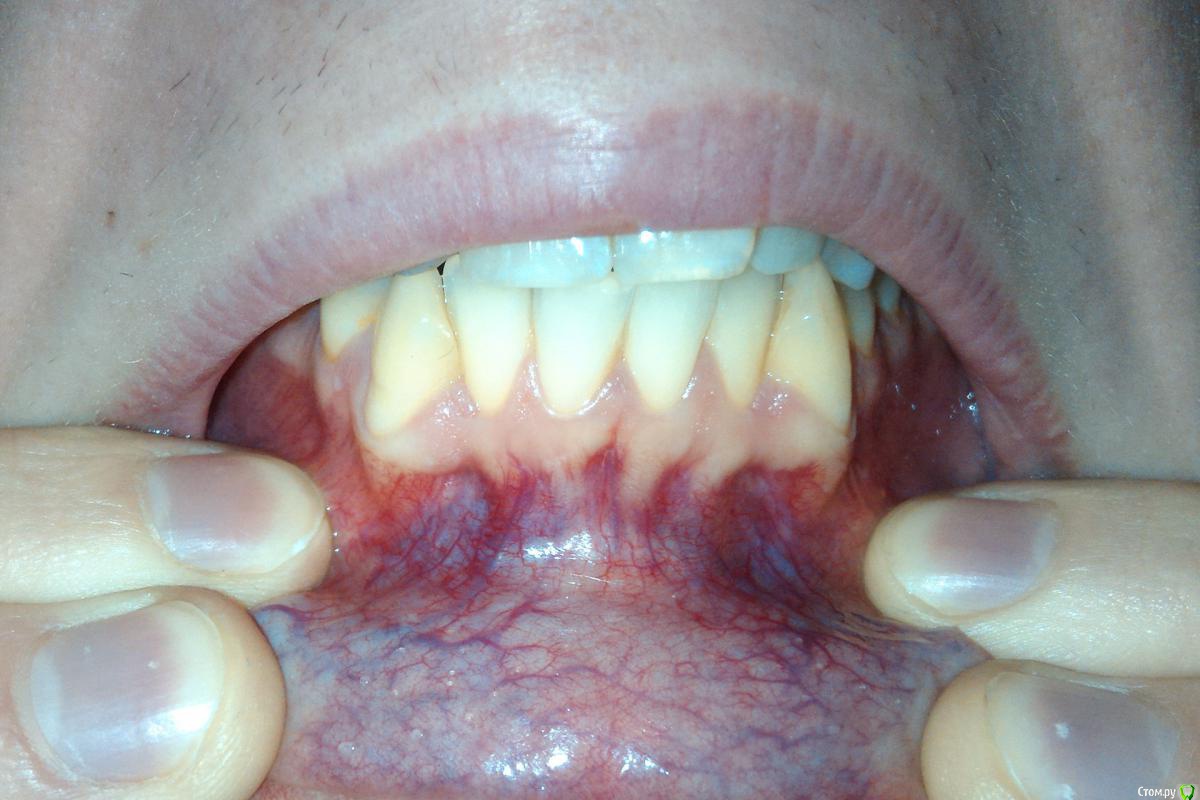

Didi Опубликовано 9 февраля, 2016 Автор Поделиться Опубликовано 9 февраля, 2016 Был на приёме у ортодонта.Ортодонт сказал что зубы двигать нельзя вообще, потому что кости вокруг зубов очень мало.Посмотрите пожалуйста, он прав?Это корни видны через десну? Ссылка на комментарий

Didi Опубликовано 12 февраля, 2016 Автор Поделиться Опубликовано 12 февраля, 2016 (изменено) сходите к другому ортодонтуА этот разве не прав? Он говорит что при передвижении зубов кости становиться меньше вокруг зубов чем были, а у меня говорит кости и так почти нету, плюс зубы крупные.Корни передних нижних зубов частично оголены.Передние корни видны сквозь дёсны. Он не прав? Я правильно вас понимаю?Проблем не будет, можно двигать? Изменено 12 февраля, 2016 пользователем Didi Ссылка на комментарий